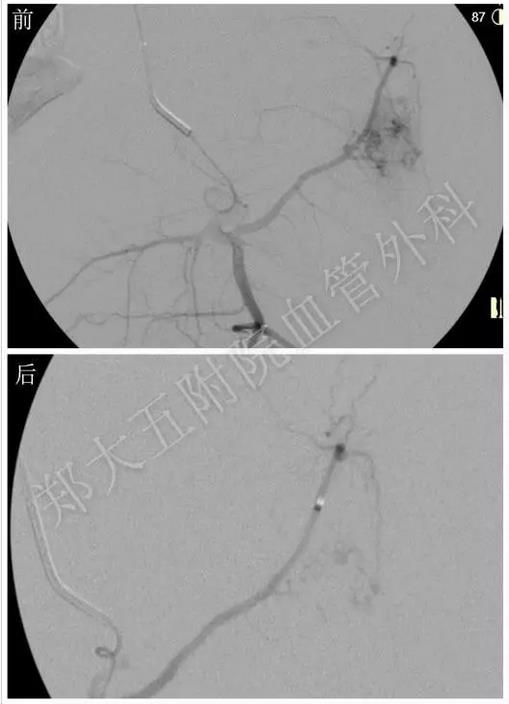

动脉造影结果证实了医生们的判断,确诊为Parkers-Weber综合征。手术过程中需要无水乙醇治疗,极易发生严重的心血管反应,但在手术麻醉科的强大技术保障下,平稳度过难关,手术顺利完成。

动脉造影证实左下肢确实存在动静脉瘘,证实为Parkers-Weber综合征

无水乙醇治疗,畸形血管团消失